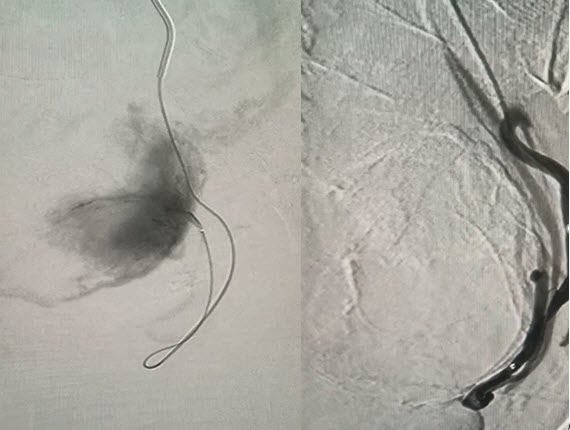

Chị H được điều trị UXTC bằng kỹ thuật can thiệp mạch (nút mạch)

Chị H. được điều trị UXTC bằng kỹ thuật can thiệp mạch (nút mạch)  tại BV ĐK tỉnh Quảng Trị

Quy trình thực hiện các Bác sỹ can thiệp mạch sẽ đưa một ống thông siêu nhỏ (Microctheter) chọn lọc vào mạch máu của khối u và sau đó bơm tắc mạch máu bằng vật liệu nút mạch sinh học, và trường hợp này khối UXTC được nút tắc mạch hoàn toàn.